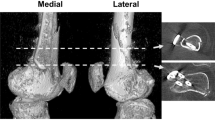

The greater and lesser tuberosities were highly prominent. In four of six samples the greater tuberosity protruded proximally, past the most proximal aspect of the humeral head. The deltoid ridge was very pronounced, coursing distally on the craniolateral surface of the bone from the greater tuberosity, attenuating before the distal third measurement level. The deltoid ridge measurement level was on average 48.12 mm (95% CI 44.66–51.58 mm), or 42% the length from the most proximal point of the humeral head. After the deltoid ridge disappeared distally the bone curved caudally (Fig. 1). There was also a highly pronounced supinator ridge on the lateral surface just distal to the distal third measurement level. In the region of the distal epiphysis, the humerus flattened craniocaudally and flared in the mediolateral plane. Both medial and lateral epicondyles were moderately pronounced.

3D reconstruction of the koala humerus from micro-CT scan using Slicer version 4.10.2. Inluding (A) medial view with left of the image being cranial, (B) lateral view with the right of the image being cranial, and (C) Caudal view with left of the image being medial. Identifying landmarks are also identified. Where h = humeral head; t = greater tuberosity; t’ = lesser tuberosity; dr = deltoid ridge; sr = supinator ridge; cf = supracondylar foramen; ec = external epicondyle; ic = internal epicondyle; ar = articular surface (radius); au = articular surface (ulna).